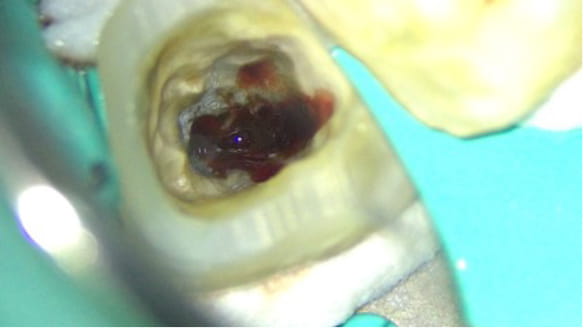

昔から噛んだ時に違和感があった。「噛み合わせが強いことが原因だろう」と言われ、削って噛み合わせの調整を何年も受けていた。詰め物が取れたことをきっかけに調べて来院。

歯の中を触ると膿がかなりでてきました。

根管の中が無菌に近い状態になるように洗浄を繰り返します。

根管の中を封鎖し、根管治療終了